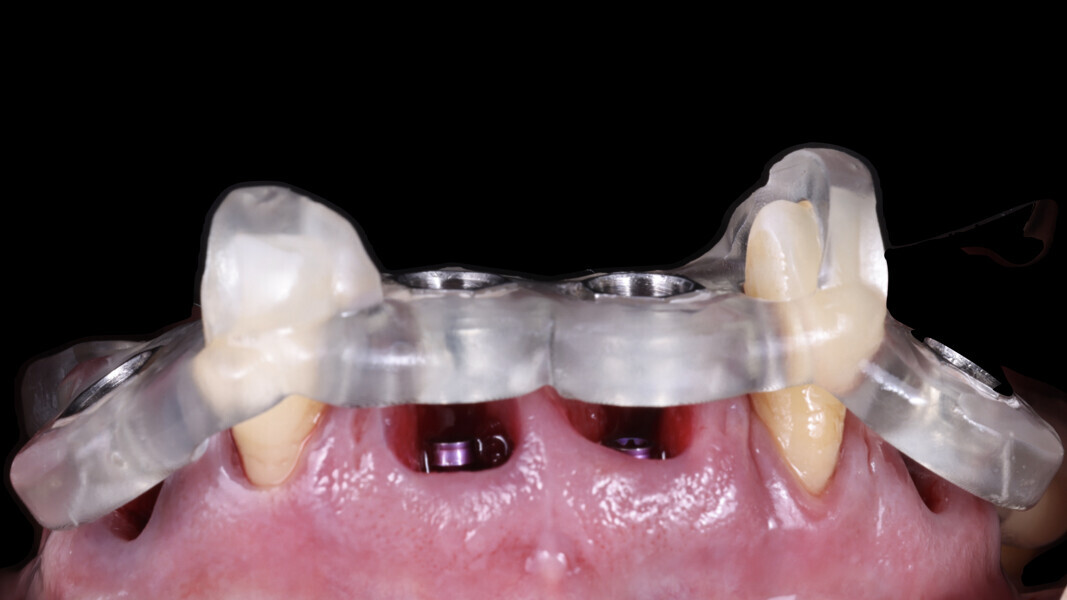

6. Placement of SmartFlag scan bodies: The scan bodies were attached. The remaining teeth served as reference points for the dental technician to align the digital impression with the preplanned design and fabricate the temporary restoration.

3. Placement of SmartFlag scan bodies: We then placed the scan bodies and captured a digital impression with them. The positioning of these scan bodies is critical for accuracy. Designed to reduce the distance between implants, they minimise inaccuracies in digital full-arch impressions. Additionally, each scan body is marked with a specific marking that helps the dentist in scanning and helps the dental technician to identify and correct any mismatches, ensuring perfect alignment (Fig. 27). The SmartFlag scan bodies are not only incredibly efficient but also user-friendly, reducing the scanning time to just 1–2 minutes. Previously, after placing the transfer, we had to splint each implant coping with pattern resin, separate them between implants and re-splint them to avoid tension in the definitive restoration. We also needed to create holes in the impression tray to allow unscrewing of the copings and removal of the impression. In some cases, a second impression with an individualised tray from the dental technician was necessary, resulting in more chair time and additional appointments (Figs. 28 & 29). With SmartFlag scan bodies, all these complications are now eliminated. Furthermore, patients with excessive gag reflexes greatly benefit from this streamlined process because it reduces discomfort.